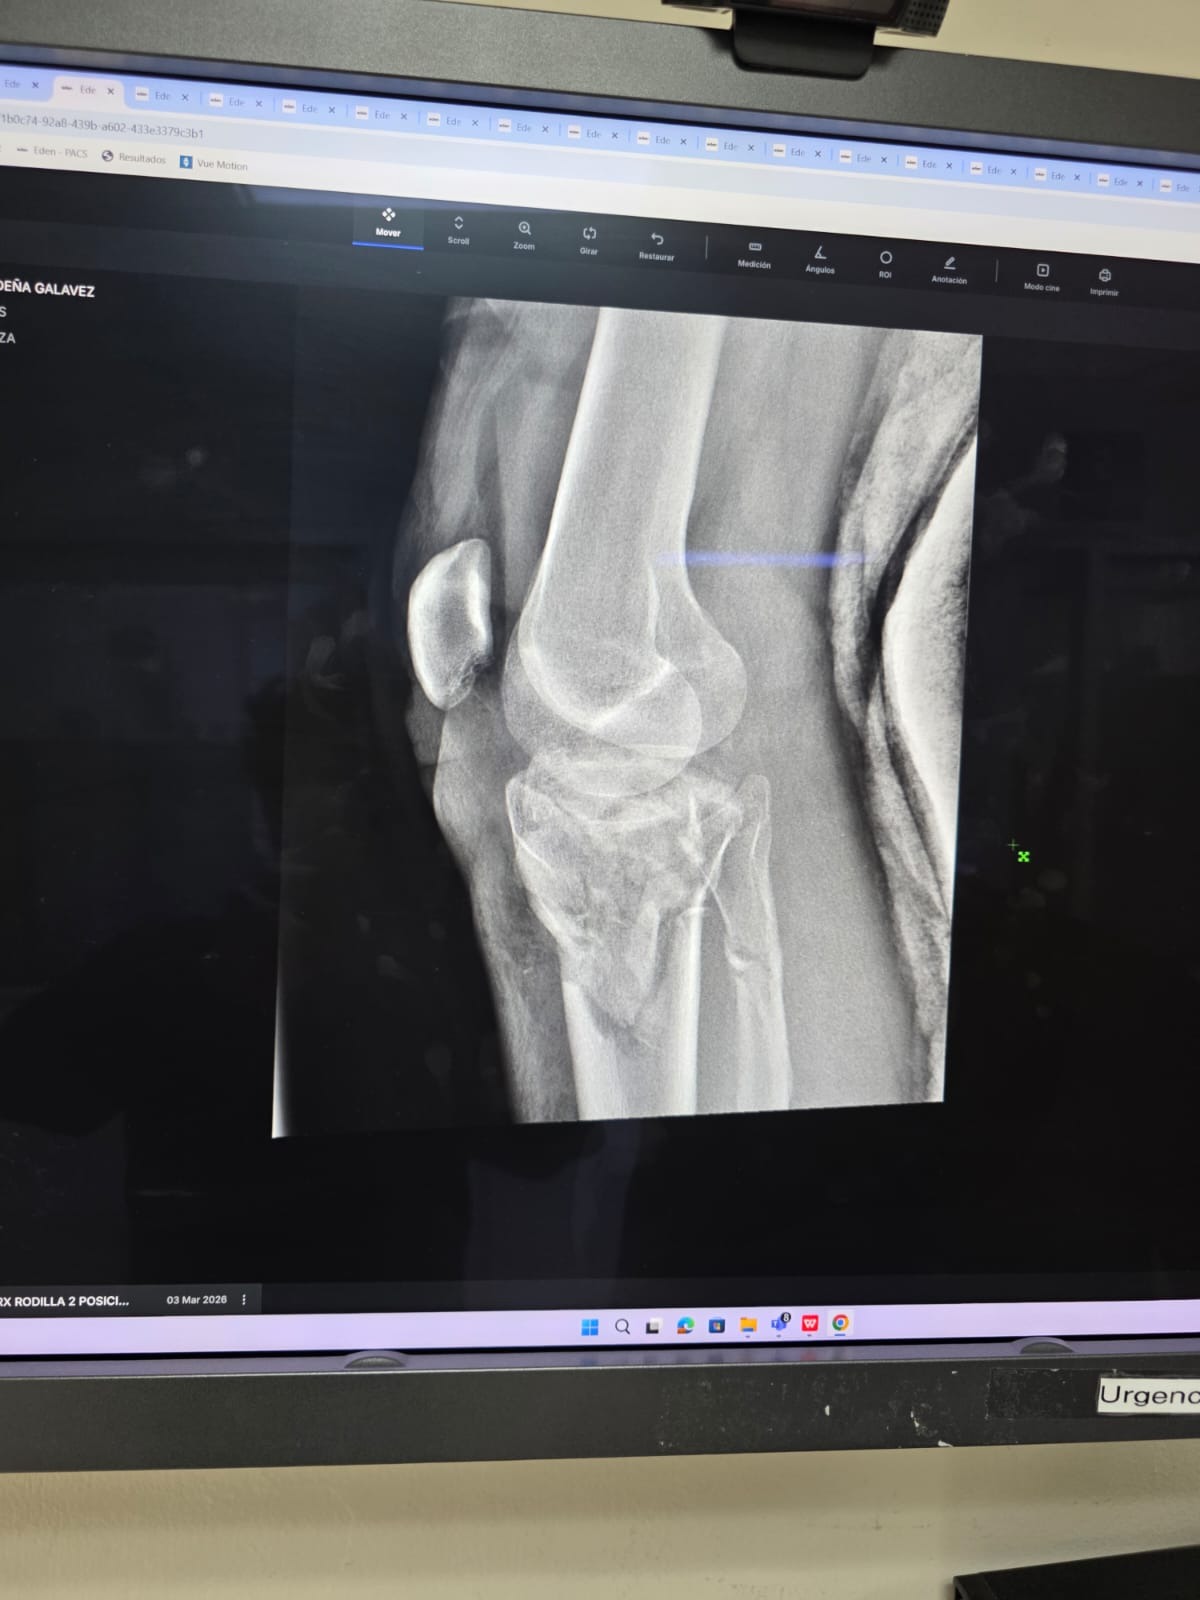

El pasado 2 de marzo, fui atropellado por una persona que huyó del lugar sin hacerse responsable. El accidente me dejó con lesiones importantes en mi pierna y rodilla, por lo que actualmente me encuentro hospitalizado y enfrentaré un proceso largo de recuperación, incluyendo cirugía y rehabilitación.

Debido a que el vehículo me arrastró, también sufrí laceraciones en la pierna, por lo que los médicos han tenido que posponer la operación hasta que las heridas cicatricen, lo que hace que el proceso sea más largo y complicado.